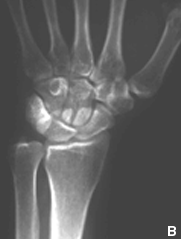

| Aumento de la densidad de partes blandas (flecha), osteopenia yuxta-articular (Cabeza de flecha blanca), erosiones en los primeros metacarpianos y huesos del carpo (cabeza de flecha negra). | Estudio normal |